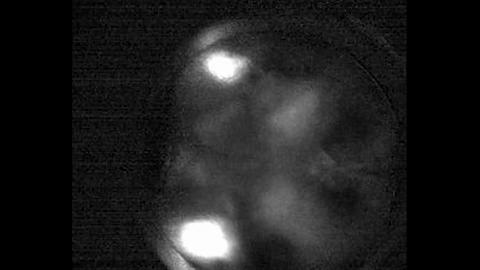

To do so, researchers developed a line of transgenic mice whose brains expressed a green fluorescent protein that lights up active neurons. They then used a customized wide-field microscope with dual lenses to capture images of the brain similar to what fMRI does in humans. Combined, the technique allows them to visualize the activity across cortex, the outer surface of the brain.

The visualization is possible because of the fluorescent protein, GCaMP6, which was developed by researchers at the Howard Hughes Medical Institute. The protein contains a calcium sensor and lights up when neurons are activated. The mouse line with GCaMP6 generated at the UO is being distributed to scientists around the world through a repository at Jackson Laboratory in Maine.

"We deliver sensory inputs -- moving images -- that trigger decision-making by the mouse," Niell said. "As the inputs are registered and behavior begins, we can watch the flow of activity across the brain. You see it all in real time, and very quickly, nearly at the speed of thought."